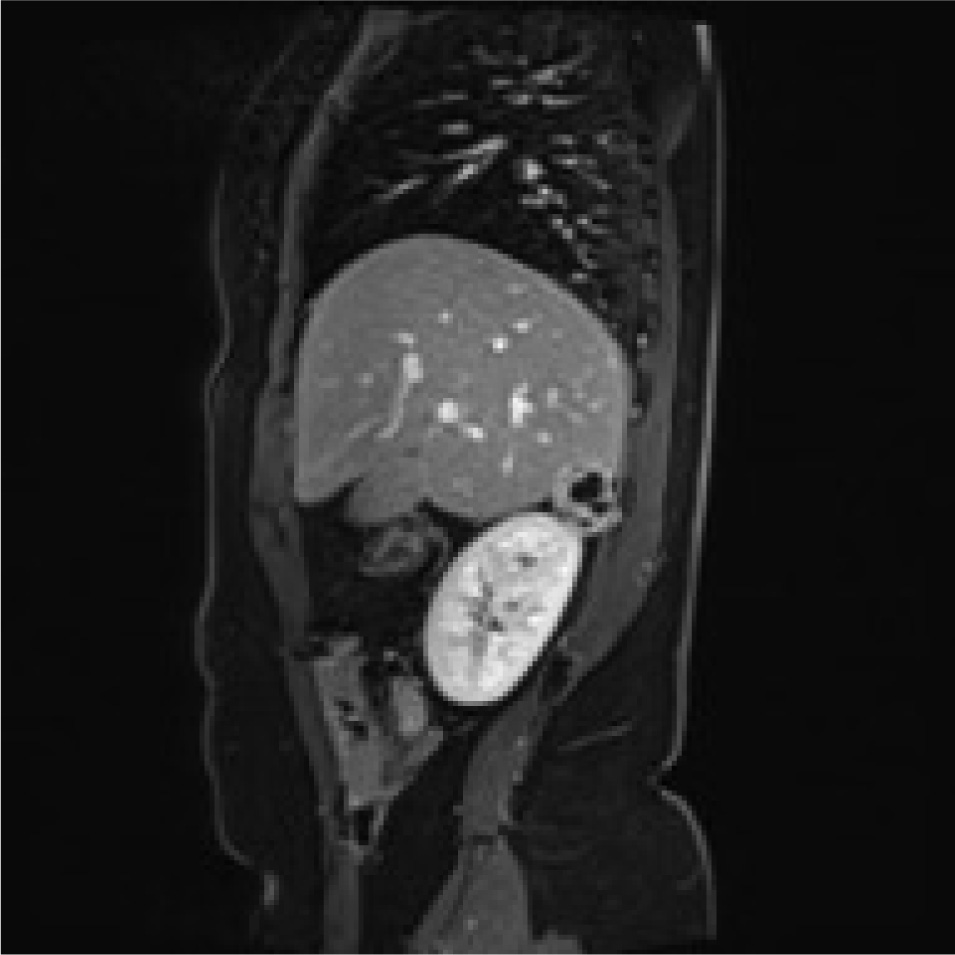

A 78-years old Moroccan woman was admitted to our department for a right flank pain without any other relevant symptoms or signs; she referred to only a light pain radiating to the epigastric region. The pain had started eight or ten months previously, she had no nausea or vomiting, she was afebrile and her vital signs were normal. She denied any contact with dogs or sheep and she had moved from Morocco to Italy in 2009. She was unemployed. Her physical examination was normal, without any significant signs or symptoms, which could suggest retroperitoneal abdominal masses. When she was a child she had the common infective diseases and at the moment of physical examination she had only an iron deficiency anemia. She underwent two Caesarean Births in 2009 and 2012. We performed routine laboratory exams on her, such as hemocromocitometric panel, major biochemical values and principal enzymes; there was no pathological alteration. She underwent ultrasound abdominal exam so we found a strange ovoidal hypoechoic formation in the right adrenal gland space; it was four centimetres in maximum diameter, and there were no signs of peripheral or central vascularization at Doppler’s exam; it was impossible to establish a sure diagnosis so we proposed a CT scan of the abdomen. The CT scan showed a solid mass of maximum diameter 5 cm, with a light peripheral vascularization and degenerative cystic areas; it had no clear linkage with either liver or with right adrenal gland. Therefore we decided to admit her to perform other imaging and laboratory exams; in fact we required an abdominal MRI which showed: “mass of 34 x 27 mm with a central cyst composed of a multilocular structure, there are signs of parietal vascularization and there aren’t signs of a clear dissection plane from kidney and liver”(image 1,2,3,4). Despite this we continued with a screening exam for HD such as indirect hemaglutination test and also hormonal exams both for adrenal cortex hormones and medullar catecholamines; all these exams were negative. We decided to perform a surgical approach to this mass, because we had to have a sure histological diagnosis of the mass; we gained the informed consent for surgical procedure. We set up the patient on the operating table in lateral left decubitus, we obtained a pneumoperitoneum with open technique and after an accurate exploration of abdominal cavity placed another three trocars to complete the procedure. We gained access to the retroperitoneal space with the same surgical steps of a laparoscopic adrenalectomy. There were significant adhesions between the unknown mass and the liver, kidney and adrenal gland. The mass was removed after a dissection through an unclear plane between liver and lesion. We extracted it into a laparoscopic bag from the access in right flank (image 5). The postoperative course was regular, without relevant complications. Unfortunately the definitive histological report was unclear. There was a significant rise in IG indirect hemagglutination one month after the surgical procedure (Indirect Haemoagglutination Assay was 1:600). Therefore we called a specialist for expert advice and finally we reached a conclusive diagnosis: Hydatid cyst localized in the retroperitoneal right adrenal gland space. Now the patient is in good health; even so, we have prescribed her a prophylactic drug treatment with albendazole.

Rm scan T2weighted sagittal image showing the adrenal mass